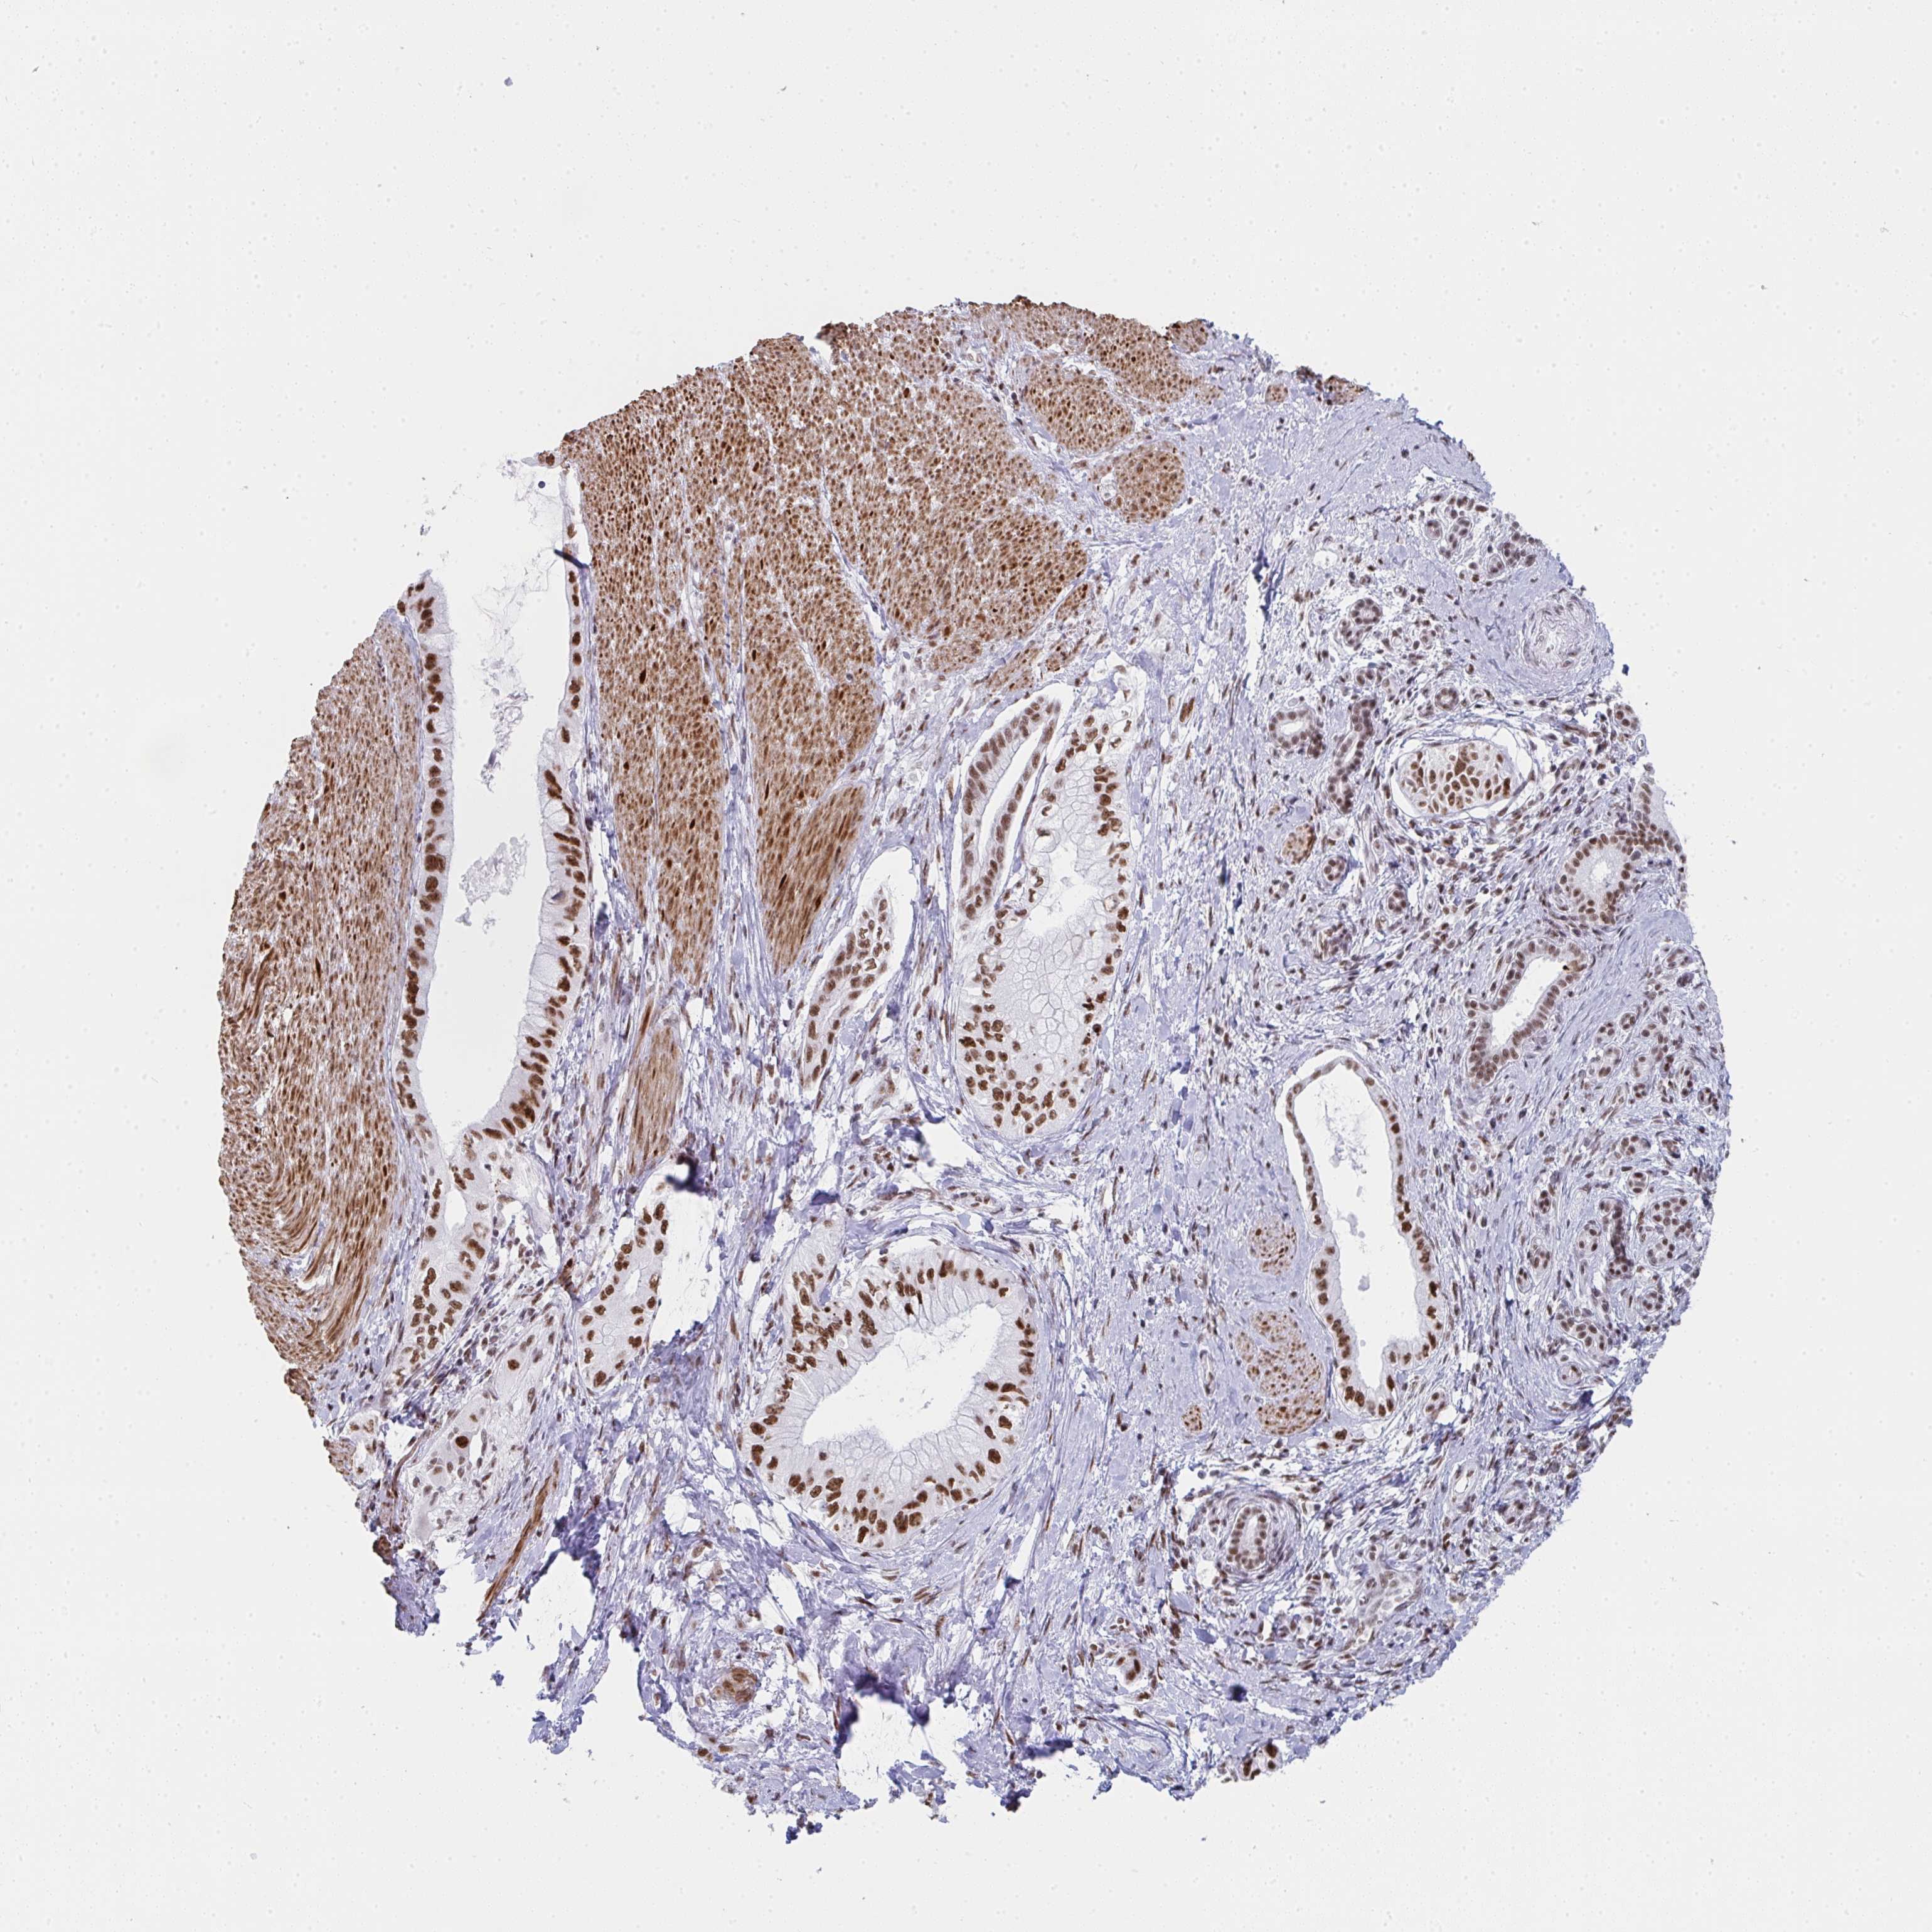

PANCREATIC CANCER - Protein expressioni

A mouse-over function shows sample information and annotation data. Click on an image to view it in a full screen mode. Samples can be filtered based on level of antibody staining by selecting one or several of the following categories: high, medium, low and not detected. The assay and annotation is described here.

Note that samples used for immunohistochemistry by the Human Protein Atlas do not correspond to samples in the TCGA dataset.

Antibody stainingi

Antibody staining in the annotated cell types in the current human tissue is reported as not detected, low, medium, or high, based on conventional immunohistochemistry profiling in selected tissues. This score is based on the combination of the staining intensity and fraction of stained cells.

Each image is clickable and will lead to virtual microscopy that enables deeper exploration of all samples and also displays staining intensity scores, fraction scores and subcellular localization as well as patient and tissue information for each sample.

Antibody HPA042050

Antibody HPA043516

Antibody CAB001718

Staining

High

Medium

Low

Not detected

Intensity

Strong

Moderate

Weak

Negative

Quantity

>75%

75%-25%

<25%

None

Location

Nuclear

Cytoplasmic/membranous

Cytoplasmic/membranous,nuclear

Adenocarcinoma, NOS